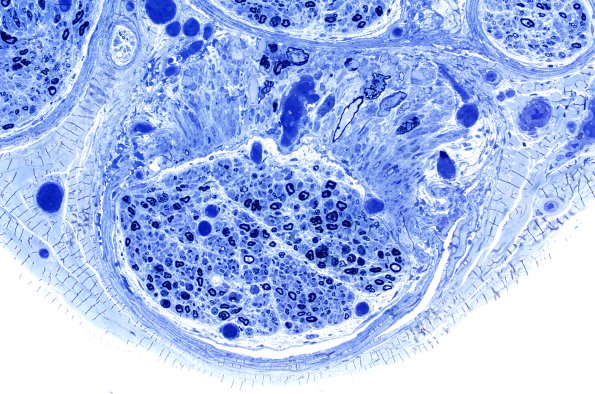

A human nerve in which one fascicle shows local damage to the perineurium causing focal axonal swellings (arrow, 12A3).